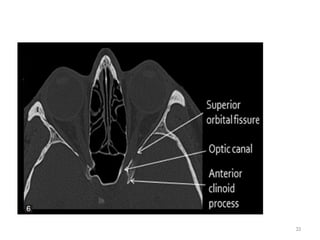

ORBITAL APEX

• Optic canal

• Superior orbital fissure

• Inferior orbital fissure

OPTIC CANAL

• Contains:

– Optic nerve

– Ophthalmic artery

• In Lesser wing of sphenoid

STRUCTURES PASSING THROUGH FORAMINA

SUPERIOR ORBITAL FISSURE

• Separates lateral wall from roof.

• Transmits the following structures:

– Oculomotor nerve (CN III)

– Trochlear nerve (CN IV)

– Abducens nerve (CN VI)

– Ophthalmic division of trigeminal nerve (CN V-1)

• Lacrimal, frontal and nasociliary Branches

– Ophthalmic vein

– Sympathetics from cavernous sinus